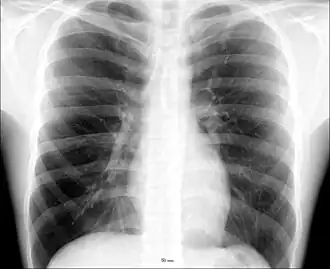

The human thorax includes the thoracic cavity and the thoracic wall. It contains organs including the heart, lungs, and thymus gland, as well as muscles and various other internal structures. The chest may be affected by many diseases, of which the most common symptom is chest pain.

The contents of the thorax include the heart and lungs (and the thymus gland); the major and minor pectoral muscles, trapezius muscles, and neck muscle; and internal structures such as the diaphragm, the esophagus, the trachea, and a part of the sternum known as the xiphoid process. Arteries and veins are also contained – (aorta, superior vena cava, inferior vena cava and the pulmonary artery); bones (the shoulder socket containing the upper part of the humerus, the scapula, sternum, thoracic portion of the spine, collarbone, and the rib cage and floating ribs).

Different types of diseases or conditions that affect the chest include pleurisy, flail chest, atelectasis, and the most common condition, chest pain. These conditions can be hereditary or caused by birth defects or trauma. Any condition that lowers the ability to either breathe deeply or to cough is considered a chest disease or condition.

The major pathophysiologies encountered in blunt chest trauma involve derangements in the flow of air, blood, or both in combination. Sepsis due to leakage of alimentary tract contents, as in esophageal perforations, also must be considered. Blunt trauma commonly results in chest wall injuries (e.g., rib fractures). The pain associated with these injuries can make breathing difficult, and this may compromise ventilation. Direct lung injuries, such as pulmonary contusions (see the image below), are frequently associated with major chest trauma and may impair ventilation by a similar mechanism.